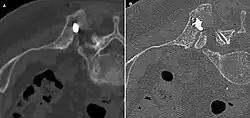

-

Axiale Computertomografie einer osteoplastischen Metastase im Schädelknochen eines Patienten mit Prostatakarzinom. Deutlich ist die Ausdehnung der Metastase über die ursprünglichen Knochengrenzen hinaus zu erkennen. -

Im Vergleich dazu eine Computertomografie osteolytischer Metastasen in den Schädelknochen einer Patientin mit Mammakarzinom. Zu sehen ist eine größere Osteolyse frontal und mehrere kleinere. -